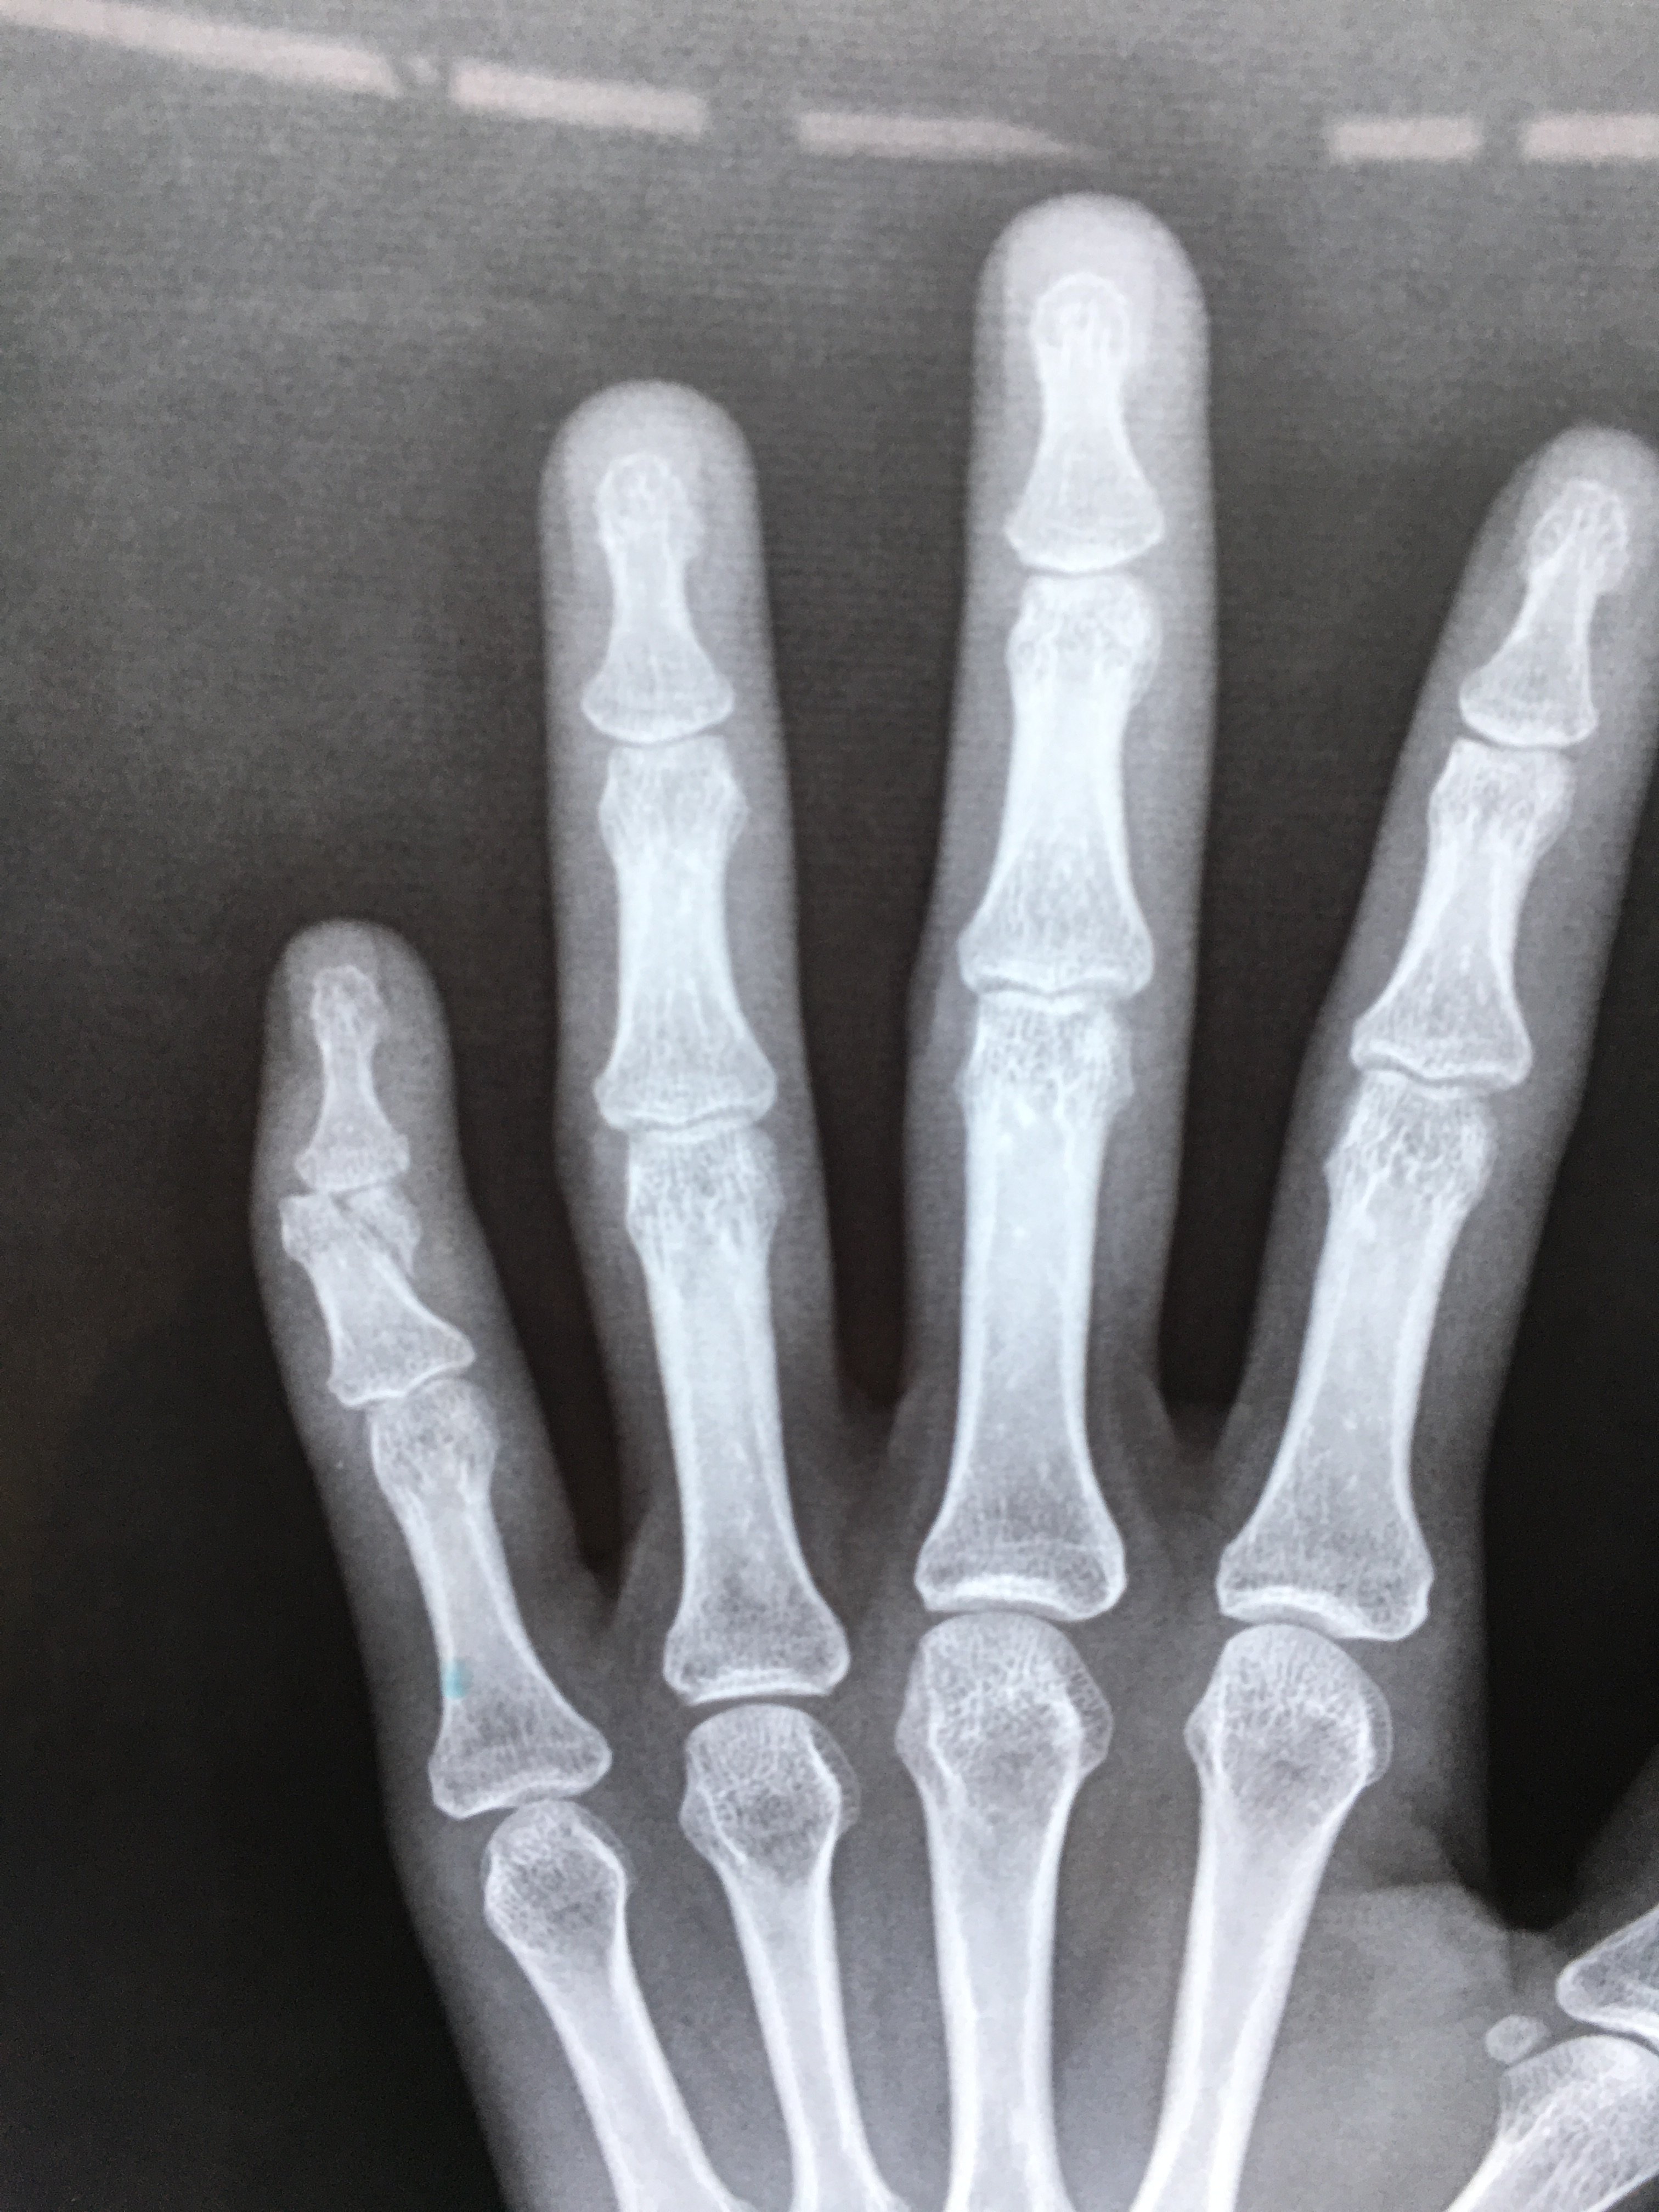

姚大夫,我孩子被别人打了!照片发现手指骨折,我们不打算找对方家长赔,您看看能不能不做手术? 等一下,让我看看孩子的手,手指有点弯,痛吗?孩子纯洁的眼神看着我,摇摇头! "不痛!" 照片发现孩子的左手 病情分析: 按照你的描述是小拇指骨折,如果骨折没有太大错位的话绑个甲板固定一下就行不需要做手术的,但是要注意不能乱活动。 指导意见: 指导意见: 最好小拇指和无名指都固定一下不要活动,一周复查看看骨折位置,一般一个月就可以去掉夹板 左手小指骨折,轻微错位 张锋 主治医师 在线咨询ta 肥城矿业中心医院普通外科 主治疾病四肢骨折,创伤的救治,内外痔,肛

1 问: 我的小指掌骨骨折了小指掌骨骨折好了以后再打不会在骨折了吧! 答: 患者朋友,你好! 你所描述的情况是小指掌骨骨折的相关问题,一般来讲,掌骨骨折通常采取保守治疗46周,对于对位关节不良或者关节部位骨折,还是首选手术治疗的。 右腿膝盖下面不见了。左腿大腿骨折钢板。右手四根小指断了,打了钢针。胸部只有两到七段。对不起,这可以评估顶级残疾。你能补偿多少? 咨询时间: 广东 汕尾 劳动工伤 骨折,伤残掌骨骨折多由直接暴力如打击或挤压伤所造成,可以为单一或多个掌骨 骨折。 骨折类型以横断和粉碎者多见,因扭转和间接暴力亦可发生斜形或螺旋形骨折。 治疗上既要充分固定又要适当早期活动,有利于手功能的恢复,对于未受伤手指绝对不能固定,以保证其他手指的活动。